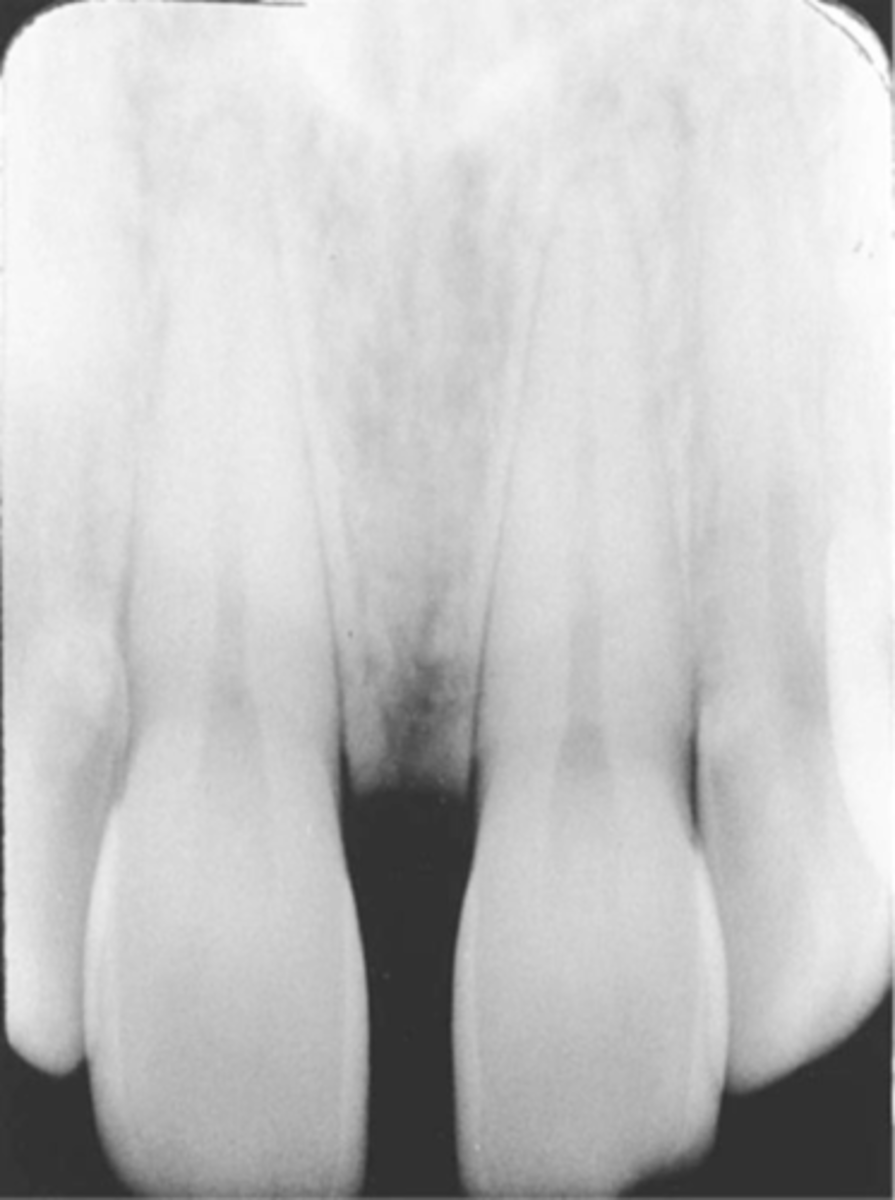

overlapped contacts

contacts are overlapped

central ray not directly through the interproximal spaces